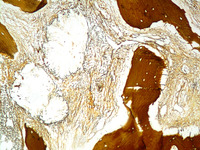

Figure 2

High power showing the oxalate crystals.